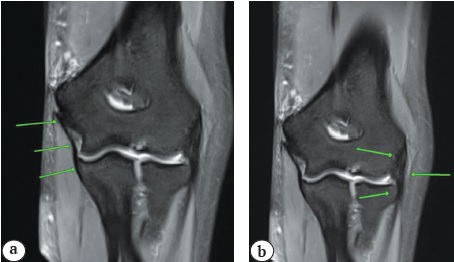

На МРТ ЛС на II уровне в аксиальной проекции измеряли расстояния от лучевого и срединного нервов и плечевой артерии до передней границы тени плечевой кости. Также от вышеупомянутых структур замеряли расстояния до УЛЭЛ и УМЭЛ (рис. 5).

Рис. 5. МРТ локтевого сустава, аксиальная проекция: 1 — условная медиальная эпикондилярная линия; 2 — плечевая артерия; 3 — срединный нерв; 4 — лучевой нерв; 5 — условная латеральная эпикондилярная линия

Результаты клинического исследования

В ходе МРТ-исследования ЛС в аксиальных проекциях на II уровне измеряли расстояния от сосудисто-нервных структур (лучевой и срединный нервы, плечевая артерия) до передней границы тени плечевой кости, а также от лучевого нерва до УЛЭЛ и от срединного нерва и плечевой артерии до УМЭЛ (табл. 4).